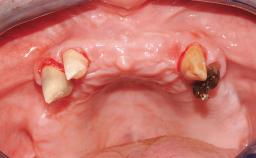

Conventional Loading of Eight Implants in the Maxilla and Final Restoration with a Full-Arch Gold-Ceramic FDP

A 35-year-old Caucasian female presenting with advanced periodontal disease involving both the maxillary and the mandibular dentition was referred for evaluation. The patient, a non-smoker in good general health, requested treatment for recurrent periodontal abscesses, tooth mobility, and discomfort during chewing, as well as restoration of her missing teeth with a fixed prosthesis to improve mastication and esthetics. All residual maxillary teeth exhibited plaque deposits, deep pockets, bleeding on probing, and class III mobility and were evaluated as hopeless. All residual mandibular teeth except tooth 37 could be maintained after periodontal therapy.

# of Implants 8

Bone Augmentation Horizontal|Staged|Vertical

Augmentation Materials Autogenous block(s)